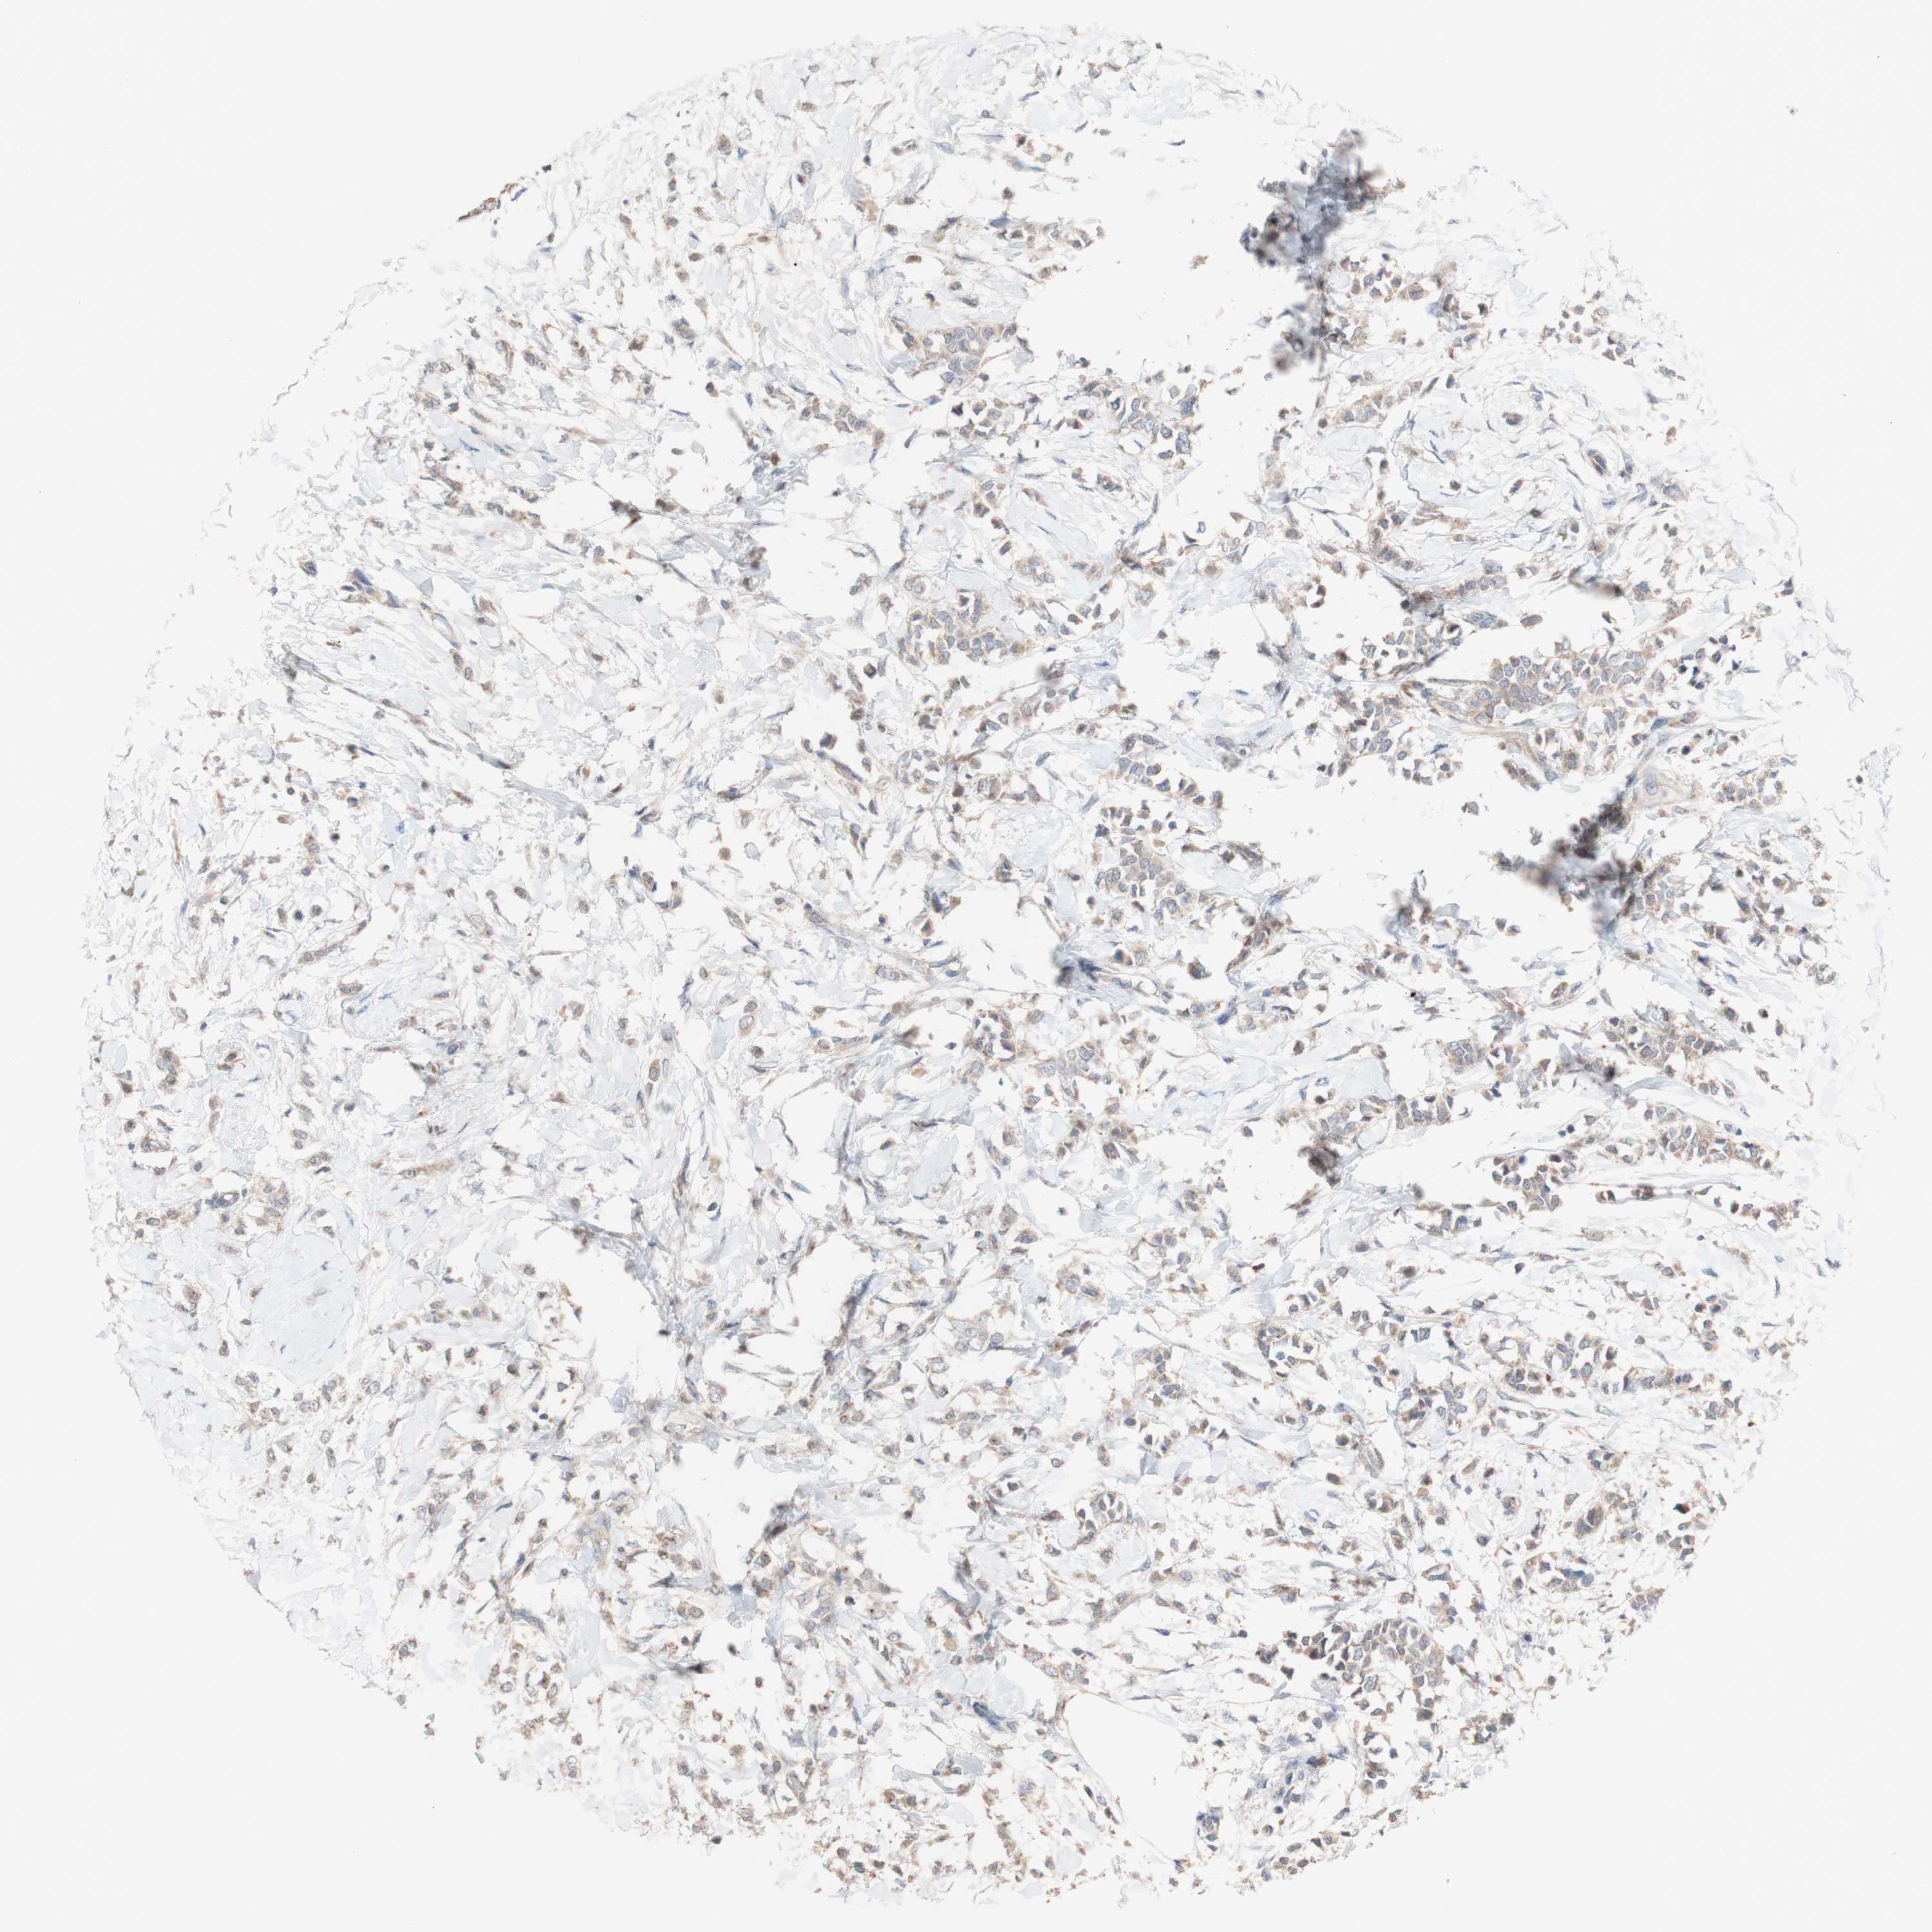

CANCER BREAST CANCER Show tissue menu

BRCA TCGA BRCA VALIDATION PROTEIN EXPRESSION